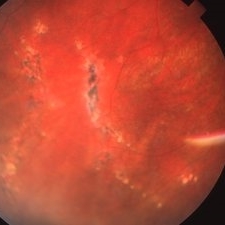

Histo and Subfoveal Neovascular Membrane

Histo and Subfoveal Neovascular Membrane

Mar 27 2019 by Gary R. Cook, MD, FACS

41-year-old white female with a large subfoveal CNVM, subretinal fluid, and hemorrhage secondary to presumed ocular histoplasmosis (POHS) OS; V.A.= 20/400.

Imaging device: Topcon VT-50

Condition/keywords: hemorrhage, peripapillary atrophy, presumed ocular histoplasmosis syndrome (POHS), subfoveal choroidal neovascularization, subfoveal neovascular membrane